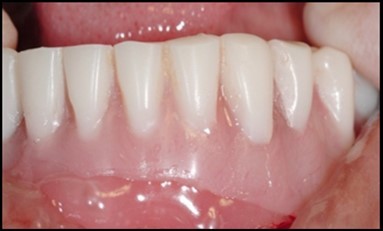

A transferable mark with an indelible pencil is placed on top of each ball abutment and old denture is seated to ideally determine the location for attachment housings. It is followed by preparation of recesses in the intaglio surface of the denture to accommodate the housings (Figure 7B). Lingual vent holes are made for escape of excess acrylic. Placement of nylon processing insert into each of the housings is done with insert seating tool. Figure 8 Seating of the attachment housing onto each ball type abutment is done (Figure 9). Undercuts are blocked out under the housing and soft tissue to prevent acrylic resin from locking the denture onto the abutment. Application of self curing acrylic is done into recessed area and around titanium housings for bonding of the housings to denture. Insertion of denture was done and guiding the patient into proper occlusion with the opposing arch. After the curing of acrylic, denture is removed. Excess acrylic is removed around the housings and lingual vent hole later it is polished (Figure 10). Replace nylon retention insert instead of processing insert into the housings. The insert must seat securely in place and be in level with the housings rim. Overdenture is seated over the ball abutments (Figure 11). Proper instructions have been given to the patient on insertion and removal of prosthesis (Figure 12). The patient was recalled at 1 week, 3 weeks, 3 months, 6 months follow up appointments.

Figure 9.Denture being inserted

Figure 11.View of denture after being cleaned and polished